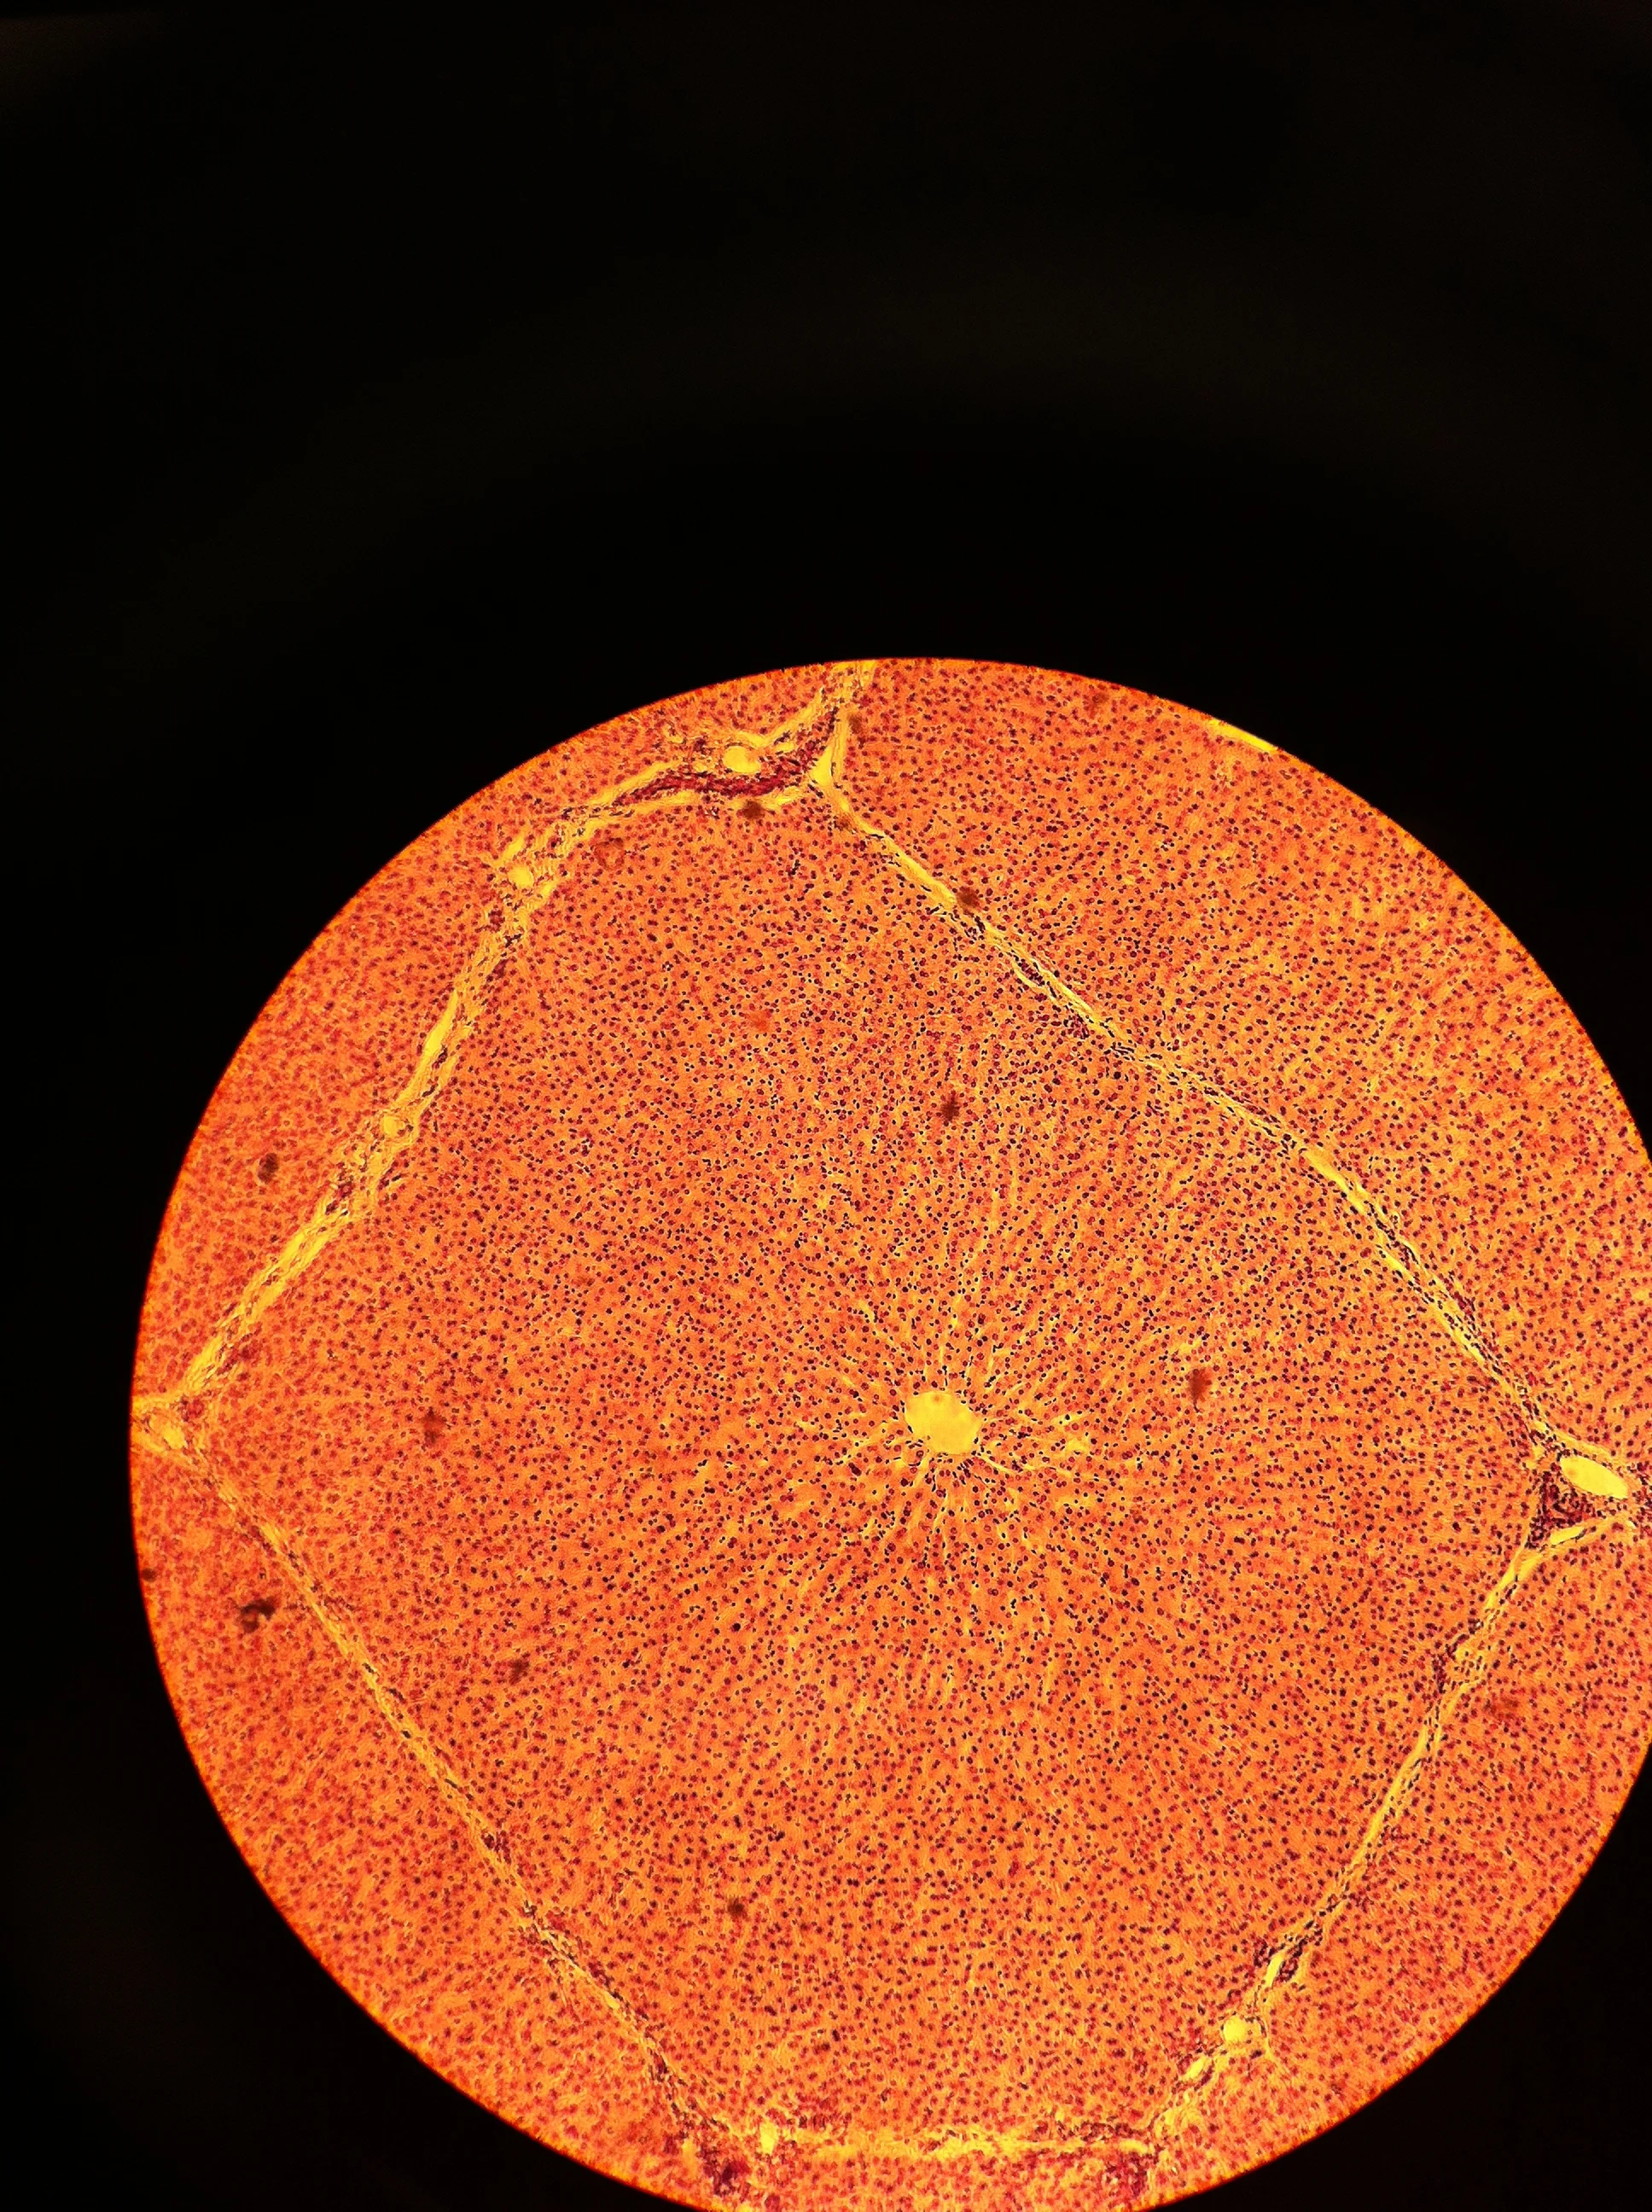

Liver 40X